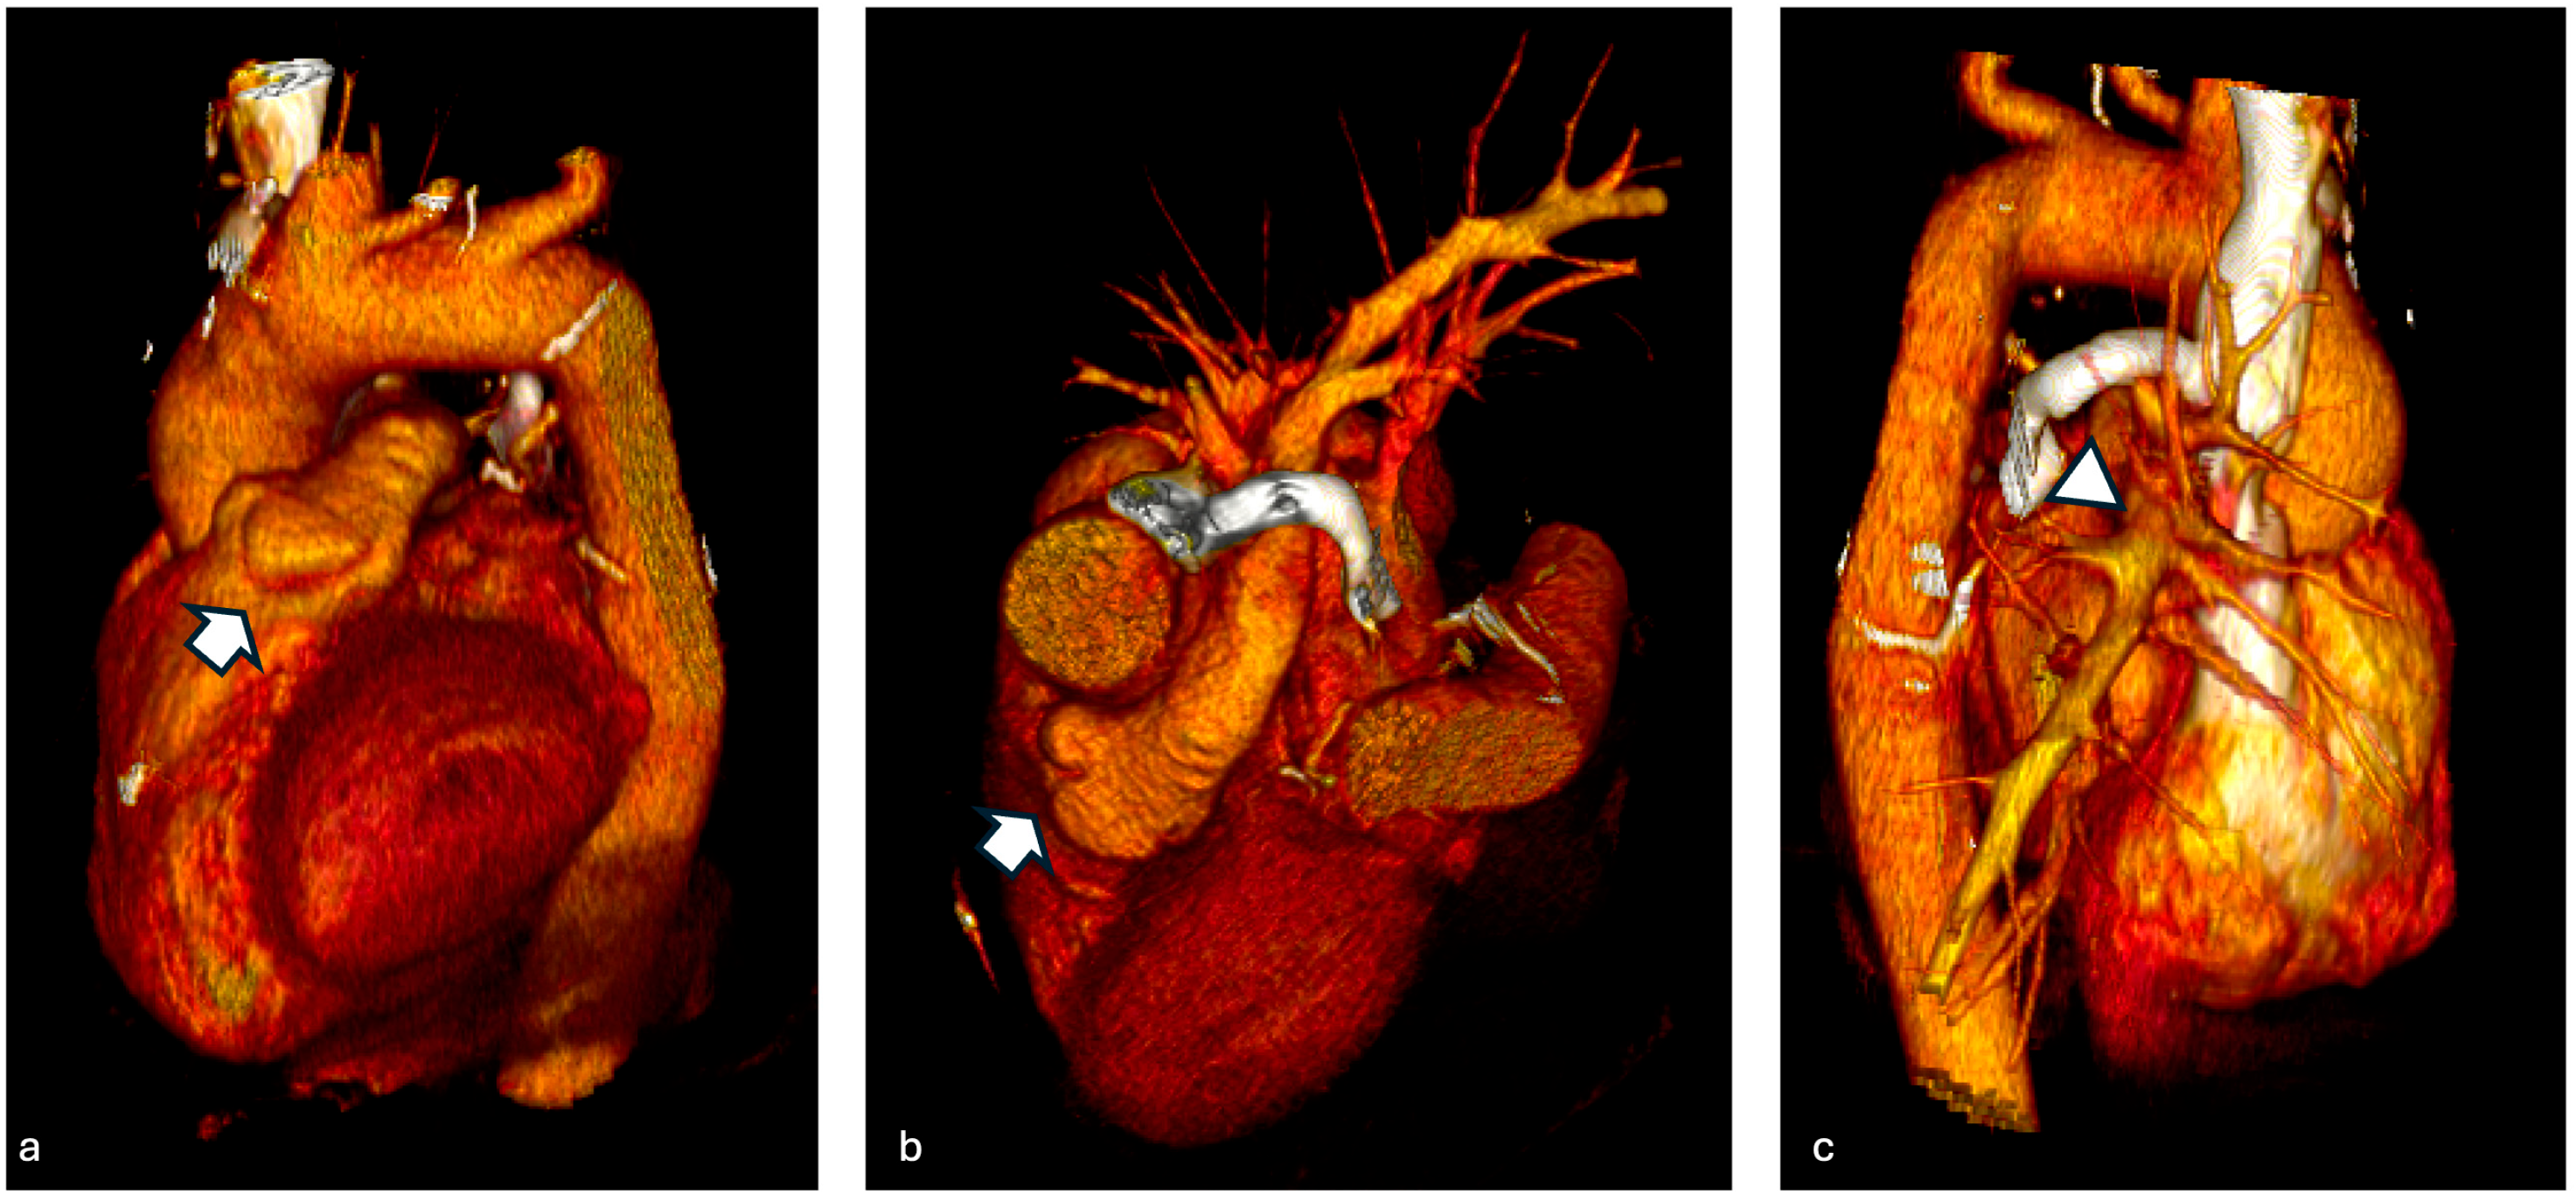

3.3. Case 3